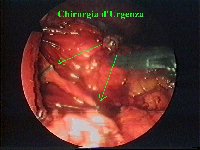

Figura 9

In questa immagine si può apprezzare la profondità alla quale spingersi per sezionare la tunica sieromuscolare.